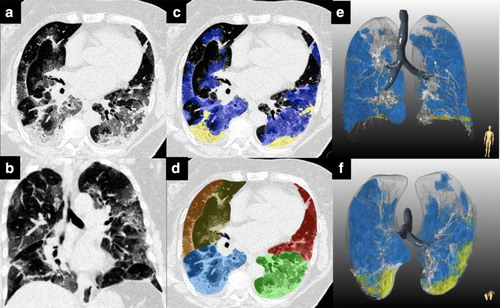

Artificial intelligence-assisted quantification of COVID-19 pneumonia burden from computed tomography improves prediction of adverse outcomes over visual scoring systems https://t.co/akRrUpxq41 #Radiology #COVID19 #ChestRad #CT @damini_dey @Piotr_JSlomka

Artificial intelligence-assisted quantification of COVID-19 pneumonia burden from computed tomography improves prediction of adverse outcomes over visual scoring systems https://t.co/akRrUpwSet #Radiology #COVID19 #ChestRad #CT @damini_dey @Piotr_JSlomka

Artificial Intelligence-assisted quantification of COVID-19 pneumonia burden from computed tomography improves prediction of adverse outcomes over visual scoring systems https://t.co/JYMrI0kBNx #Radiology #ArtificialIntelligence #COVID19 #ChestRad @damini_dey @Piotr_JSlomka

Artificial Intelligence-assisted quantification of COVID-19 pneumonia burden from computed tomography improves prediction of adverse outcomes over visual scoring systems https://t.co/42ceGkWgBC